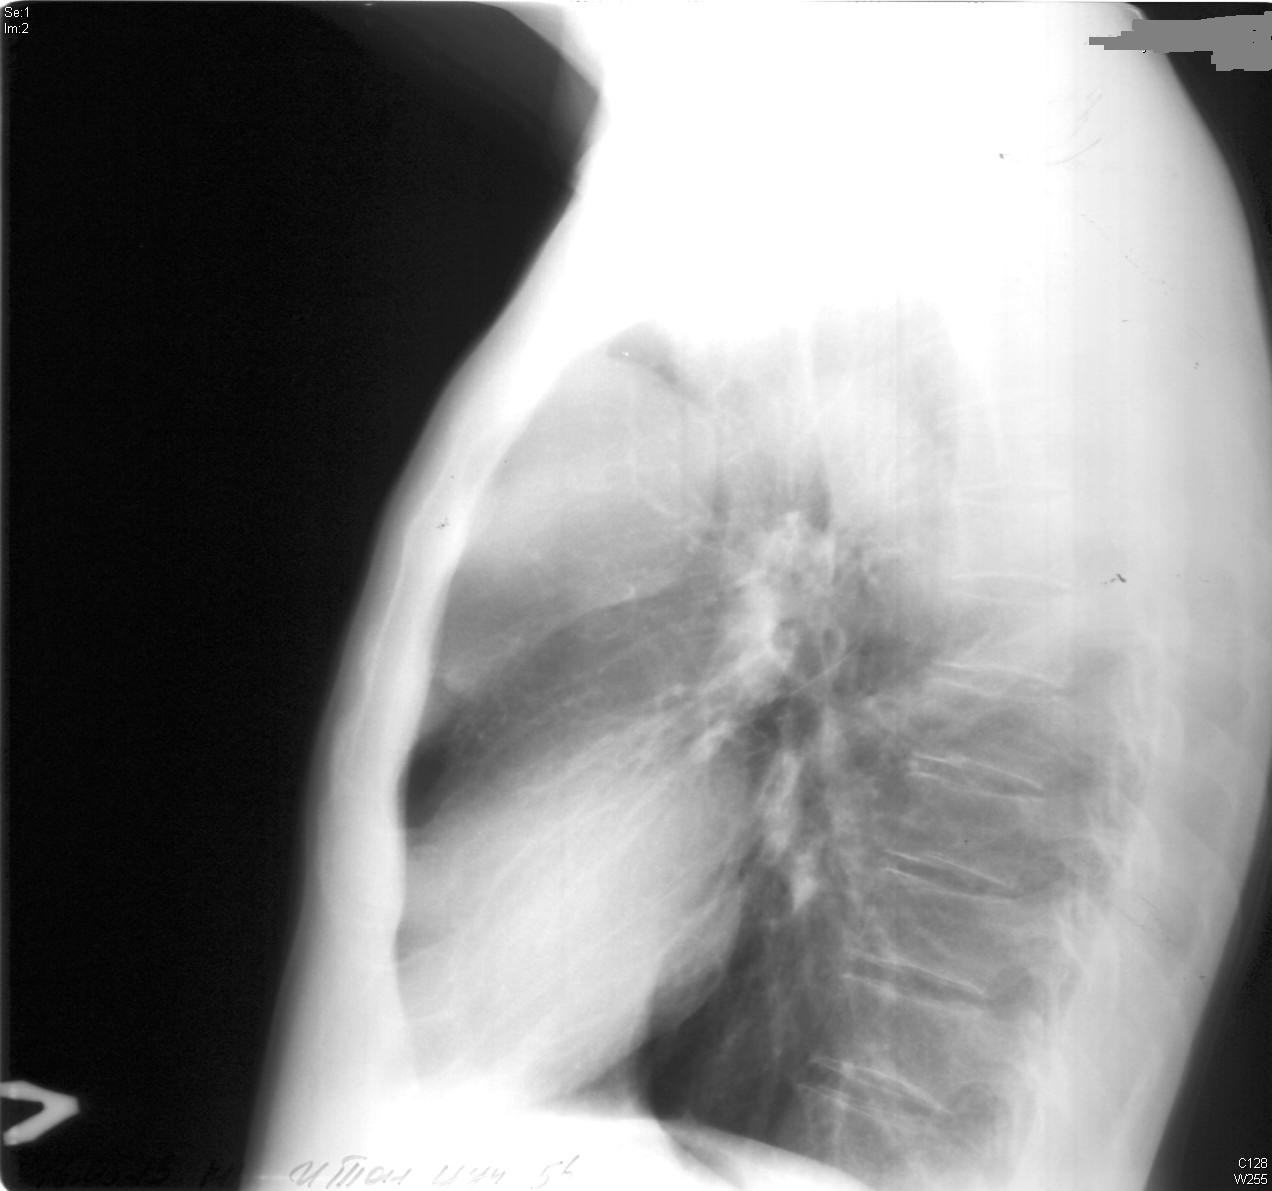

M/56

4°³¿ù ÀüºÎÅÍ ¹ß»ýÇÑ Èí±â½ÃÀÇ ÈäÅë

±âħ °¡·¡ ÀÖÀ½

5ÀÏ ÀüºÎÅÍ ¾ÇÈ­µÇ¾î ³»¿øÇÔ

2012³â 11¿ù Chest PA, lateral

2013³â 5¿ù Chest PA, lateral ÀÔ´Ï´Ù.

lateral »çÁø °øºÎ¸¦ À§ÇØ Á¤Áö¿¹ ¼±»ý´ÔÀÌ ÃßÃµÇØ ÁֽŠȯÀÚ ¿µ»óÀÔ´Ï´Ù.